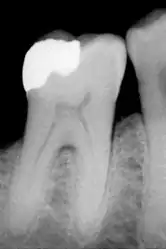

![]() الضرس المسمى | |